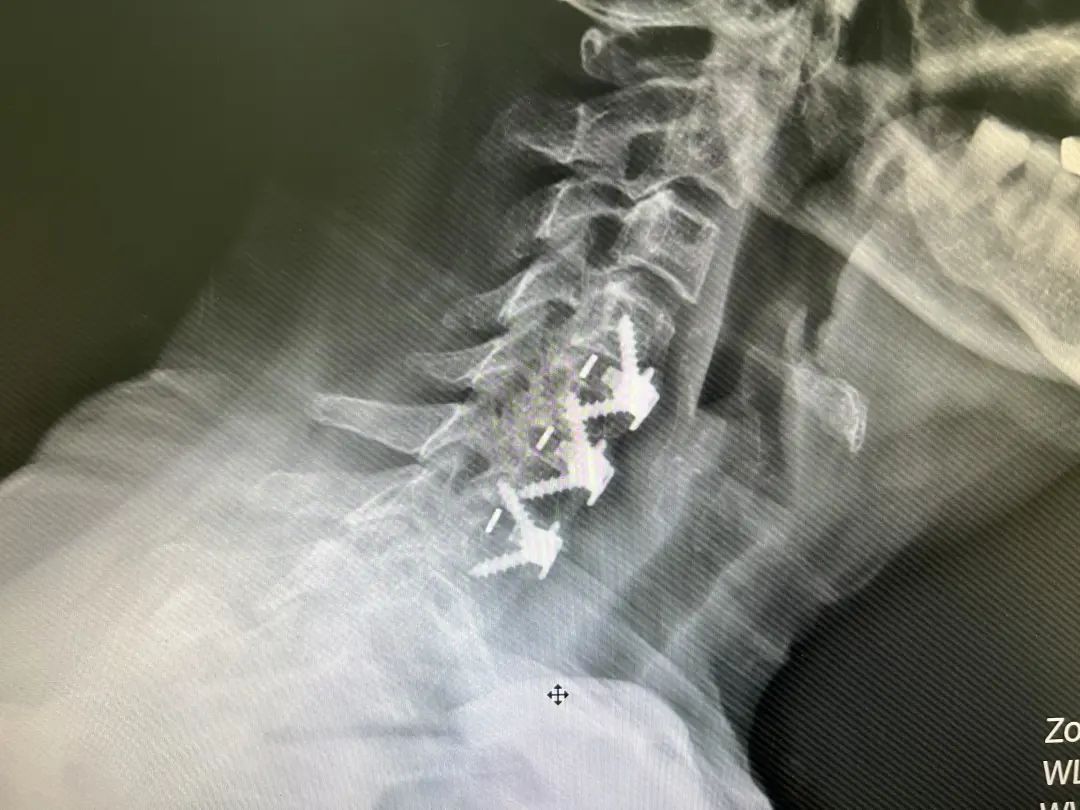

2022年3月9日,在麻醉科及骨伤科四病区的配合下,李智奎副主任医师团队为隆奶奶实施了颈椎间盘切除椎间植骨融合术。在科室医护人员的精心治疗与护理下,术后隆奶奶一切恢复良好,于2022年3月16日出院,出院时隆奶奶告诉医护人员上肢麻木情况已有很大改善。